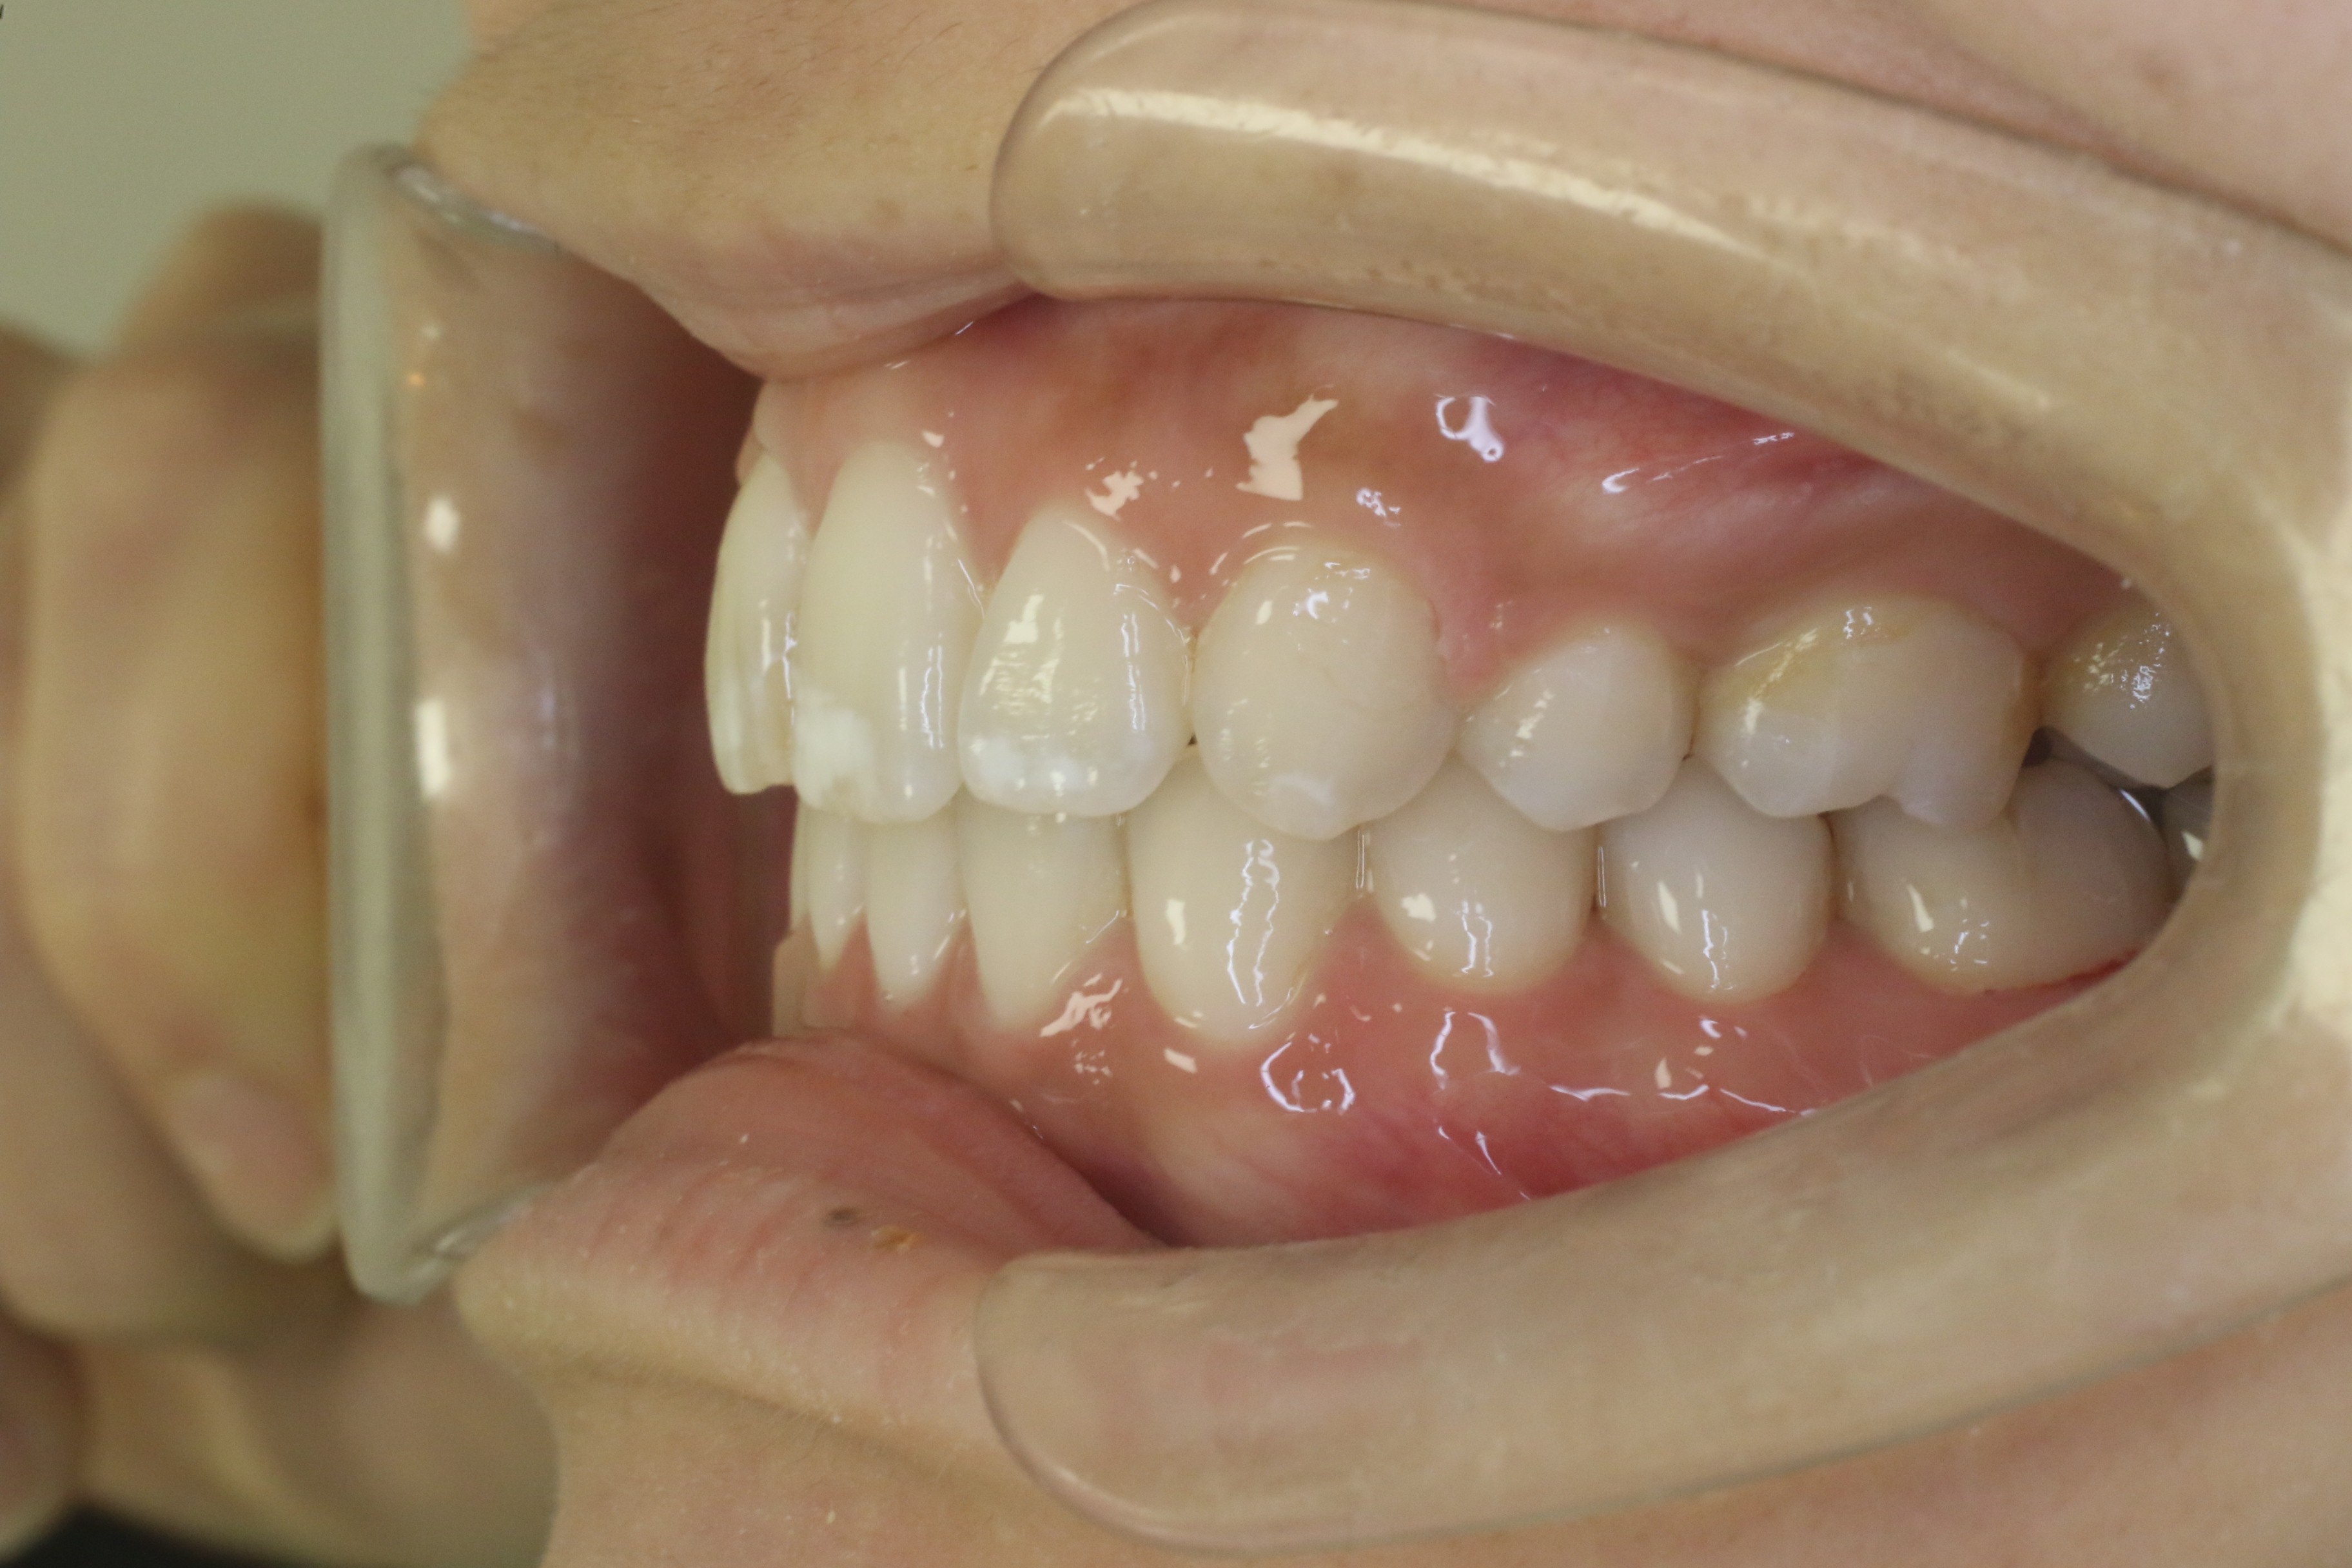

すきっ歯を治したい

年齢層 20代

性別 女性

主訴 【主訴】すきっ歯を治したい 【診断・症状】空隙歯列、1,1正中離開

治療費用 検査・診断:38,500-/裏側矯正治療:1,397,000-(※全て税込)

治療期間 約1年8か月(22回)

抜歯 無(非抜歯)

矯正の装置 裏側矯正(舌側矯正)

副作用、リスク 歯肉退縮,歯根吸収,疼痛,咬合の違和感,装置の違和感,虫歯,歯肉炎

case6_すきっ歯_before

Before

case6_すきっ歯_after

After